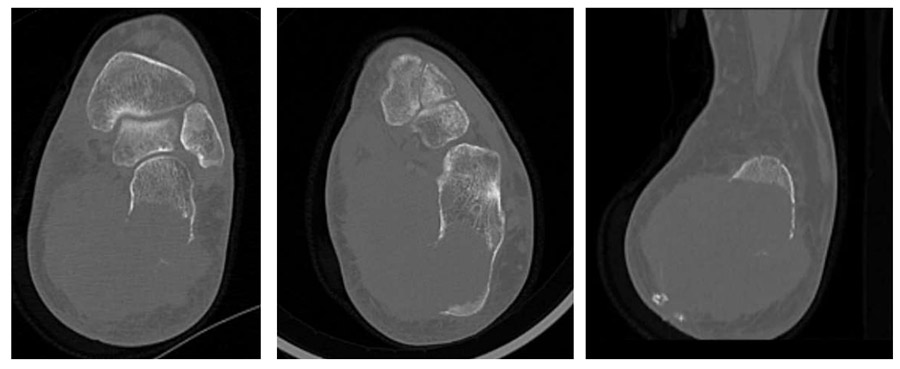

Ameliyat Öncesi: Tomografide kalkaneusta ciddi harabiyete neden olan yumuşak doku kitlesi görülmekte